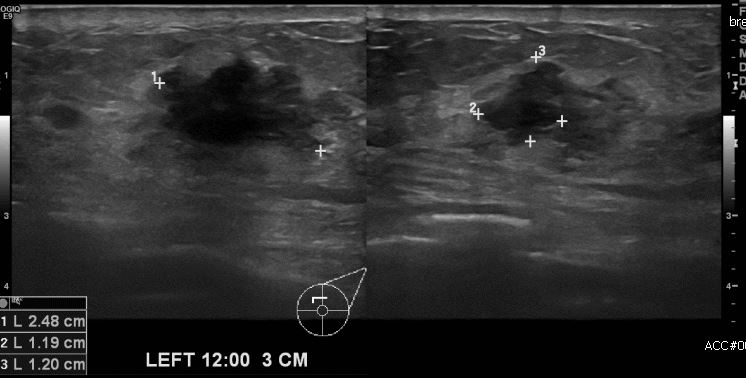

상기환자 좌측 유방의 멍울과 통증으로 내원하신 70대 여성분으로 좌측 12시 방향에서

3cm 떨어진 거리의 만져지는 멍울 조직검사 시행하여 좌측 침윤성 유관암 진단 되었습니다.